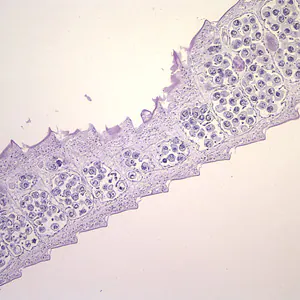

Hymenolepis diminuta eggs in wet mounts.

Hymenolepis nana egg in wet mounts.

Hymenolepis nana eggs, zinc PVA trichrome stain.